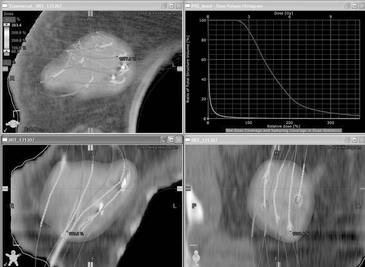

Dávková distribuce 3D brachyterapie lůžka tumoru ve 3 rovinách

V odstupu 7-10 dnů od operace provedeme

plánovací CT (posun 3 mm) a následně vlastní plán. Při konturaci

určujeme lůžko nejen na podkladě kavity a klipů patrných na

plánovacím CT, ale rovněž i dle lokalizace afterloadingových

katetrů. Denzní obraz kavity na CT řezech totiž není zcela totožný

s primárním lůžkem tumoru. Tento obraz se navíc mění v čase -

tvarem i velikostí. Dle Tersteega (JJROBP 2009) dochází i při

vlastní radioterapii k redukci objemu kavity průměrně o 62% a to o

1,3 cm3/den. Odlišnost denzní kavity a vlastního lůžka

tumoru je graficky prokazatelná i u našich pacientek. U části z

nich totiž procházely všechny katetry z některé z rovin zcela mimo

denzní obraz kavity patrné na plánovacím CT. Brachyterapii